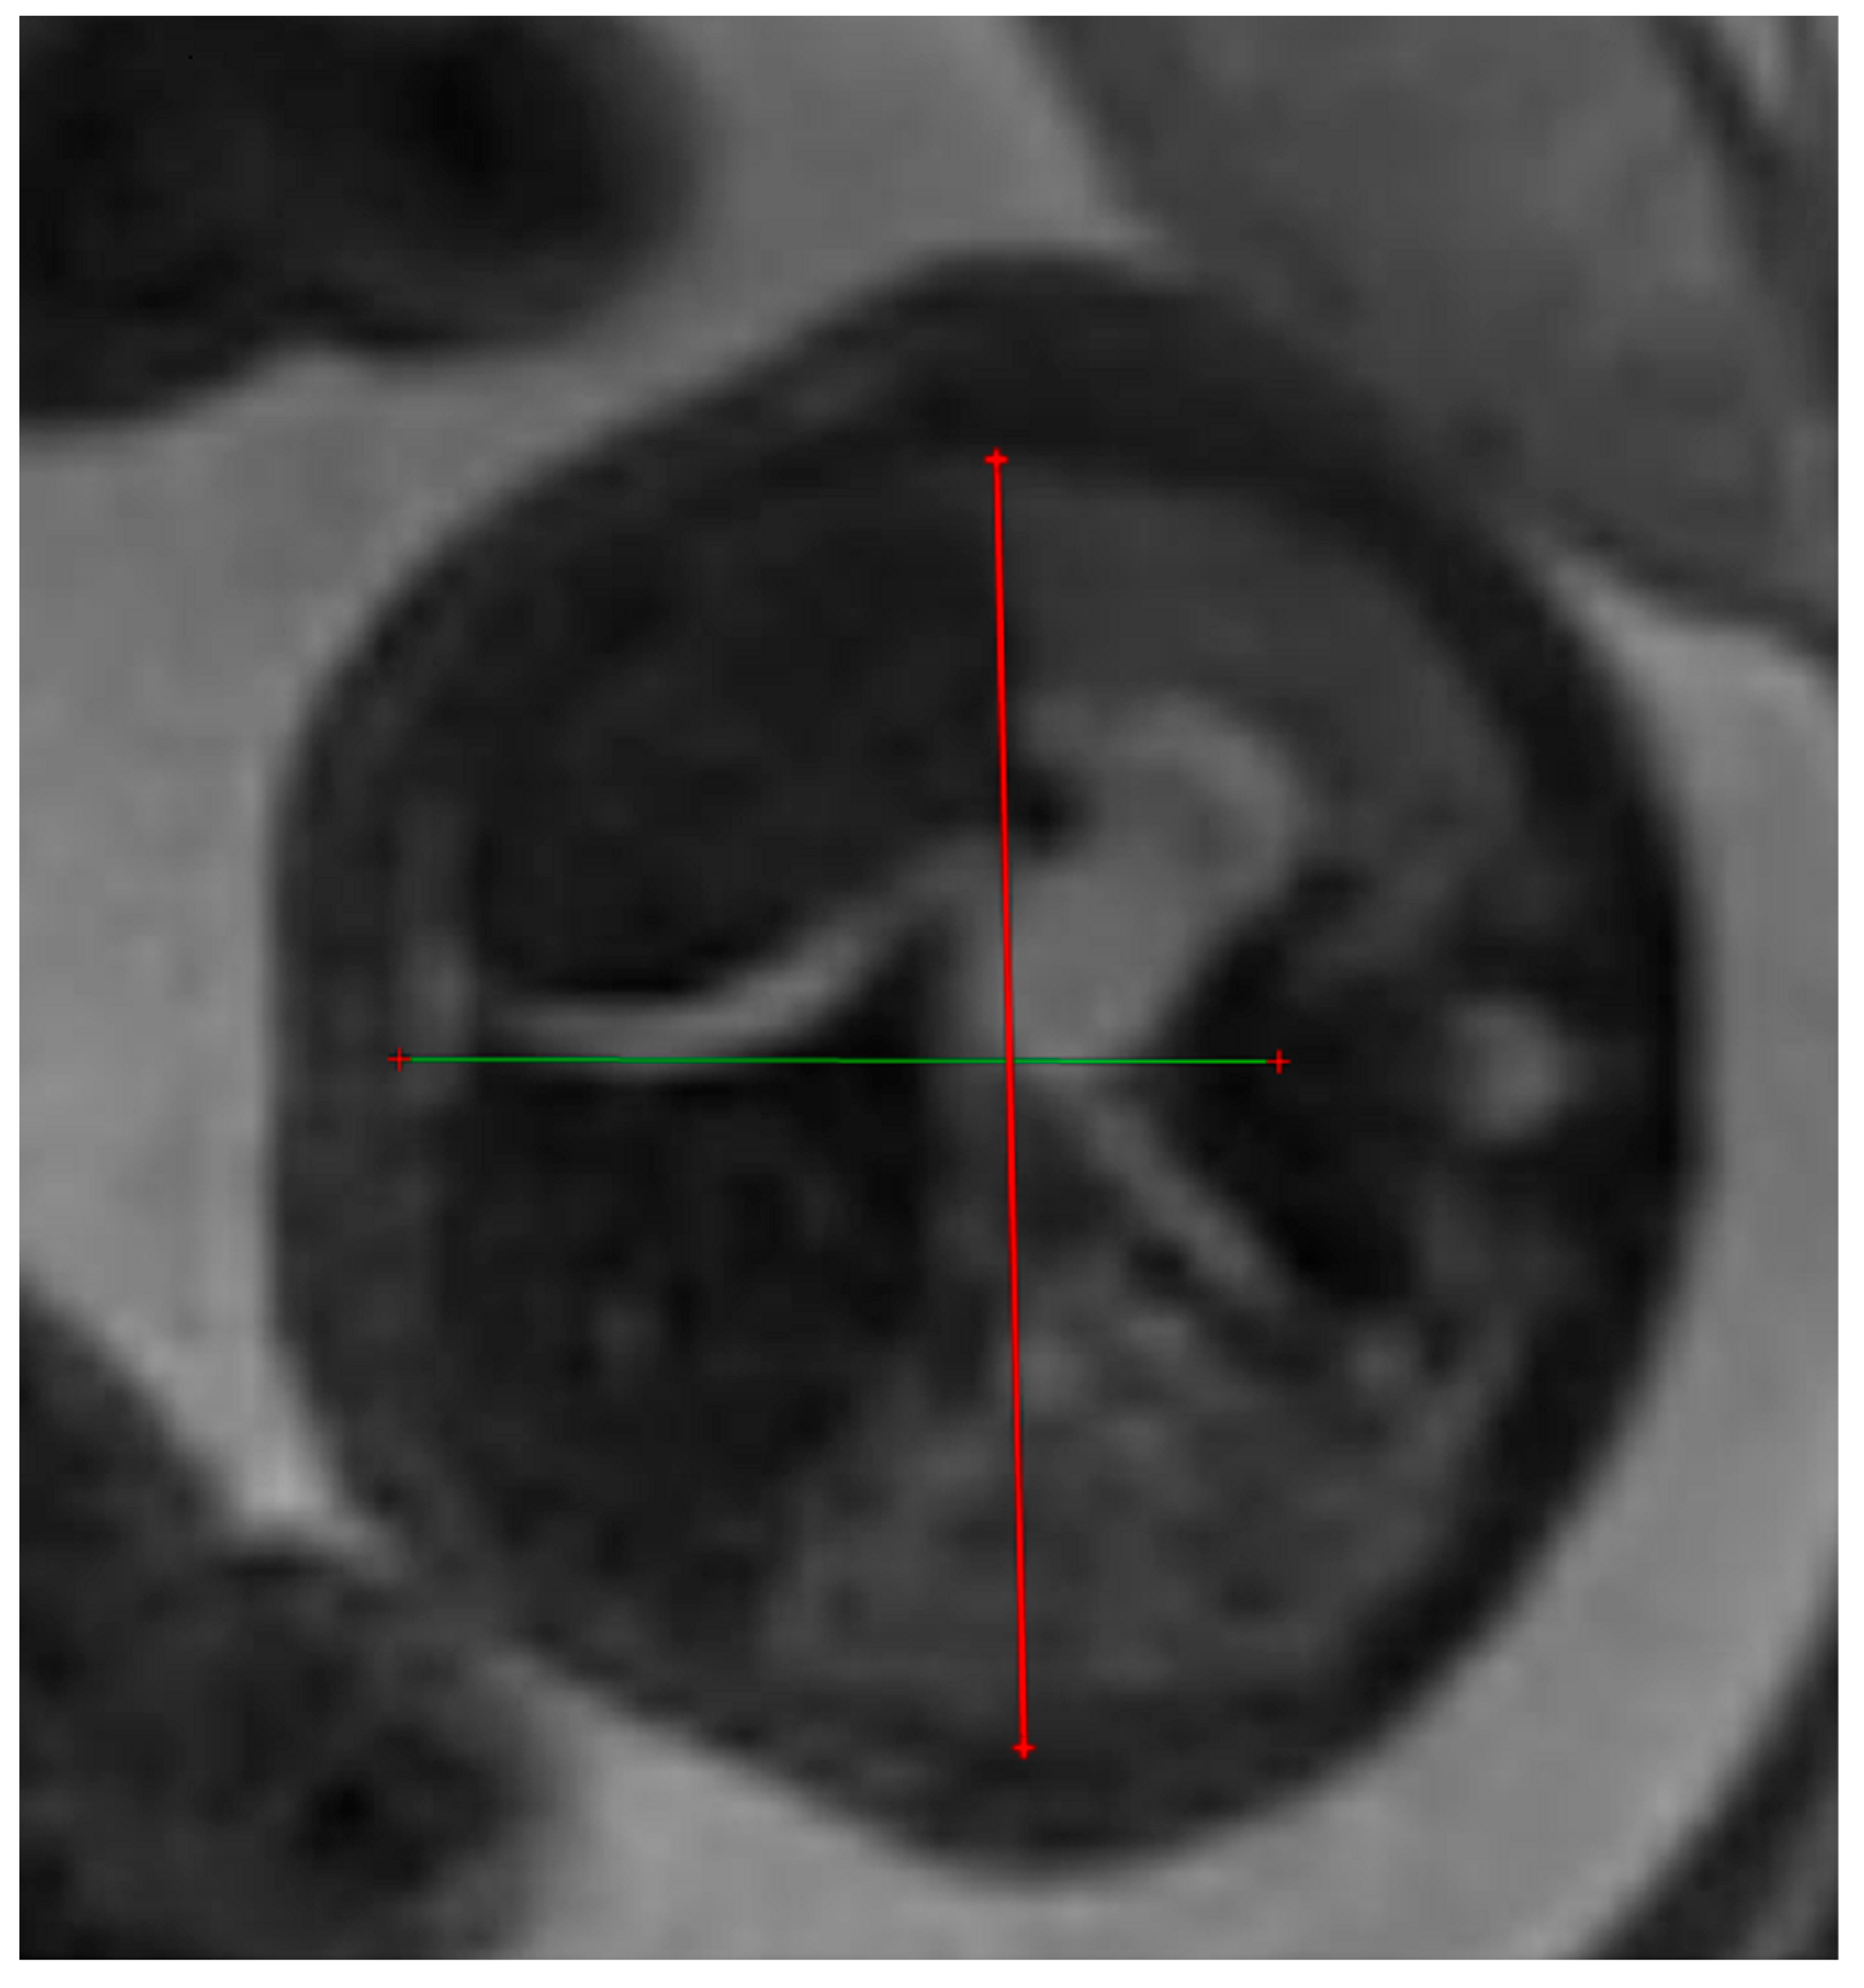

The thoracic transverse and anterior–posterior diameters were measured in the axial plane at a level equivalent to the ultrasound four-chamber section. The measurements were made from the internal face of the ribs for the transverse diameter and from the posterior face of the sternum to the vertebral body for the anterior–posterior diameter respectively. Figure 3 and Figure 4.

Figure 3. MRI axial T2 weighted image of the fetus showing how to measure the anterior–posterior and transverse diameters of the thorax, using the RadiAnt DICOM Viewer program, version number 2022.1.1. The green lines represent the lug transverse and anterior-posterior diameters.